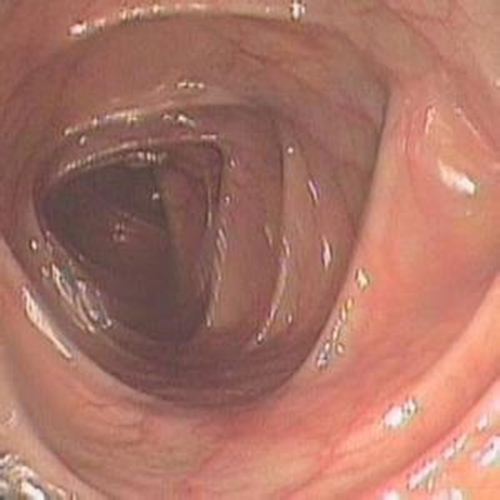

纖維結腸鏡檢查

慢性結腸炎圖片

早期慢性結腸炎的